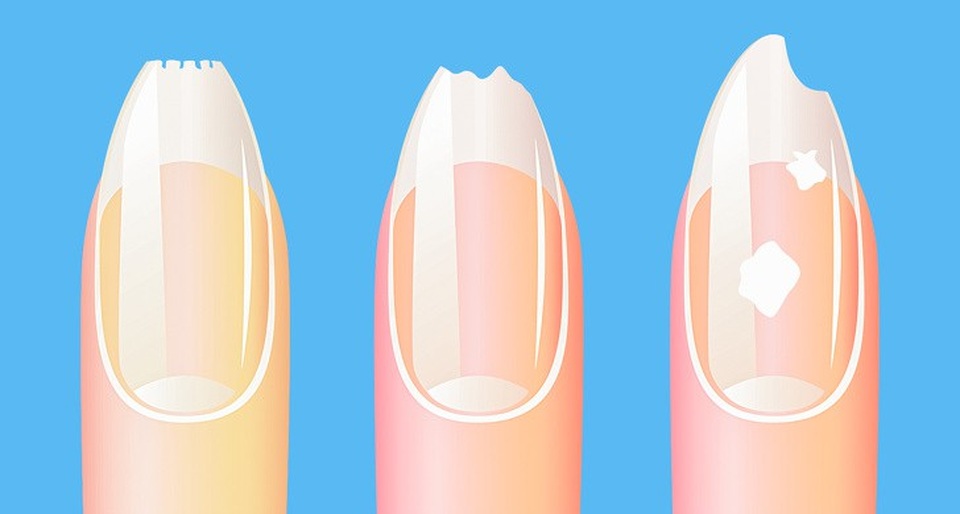

3. Móng tay dễ gãy

Bất kì một sự thay đổi nào về màu sắc hoặc cấu trúc của móng tay đều là dấu hiệu đáng báo động. Móng tay mỏng, nhợt nhạt là dấu hiệu thiếu máu và thiết sắt. Móng tay vàng là vấn đề rối loạn gan và dạ dày. Móng tay có đốm trắng và sọc cho thấy sự thiếu kẽm, đồng và i ốt. Móng tay giòn dễ gãy khi cơ thể thiếu vitamin, canxi, sắt và beta-carotene.